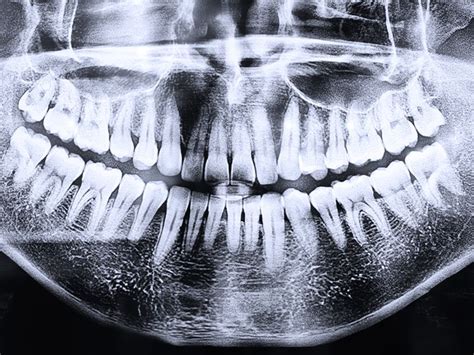

El segundo paso a seguir, es hacerte una radiografía panorámica para dar un mejor diagnóstico. Después de realizarte la radiografía panorámica nuestros especialistas te harán una exploración minuciosa del estado de tu salud bucodental y poder proponer el mejor plan de tratamiento a tus necesidades.